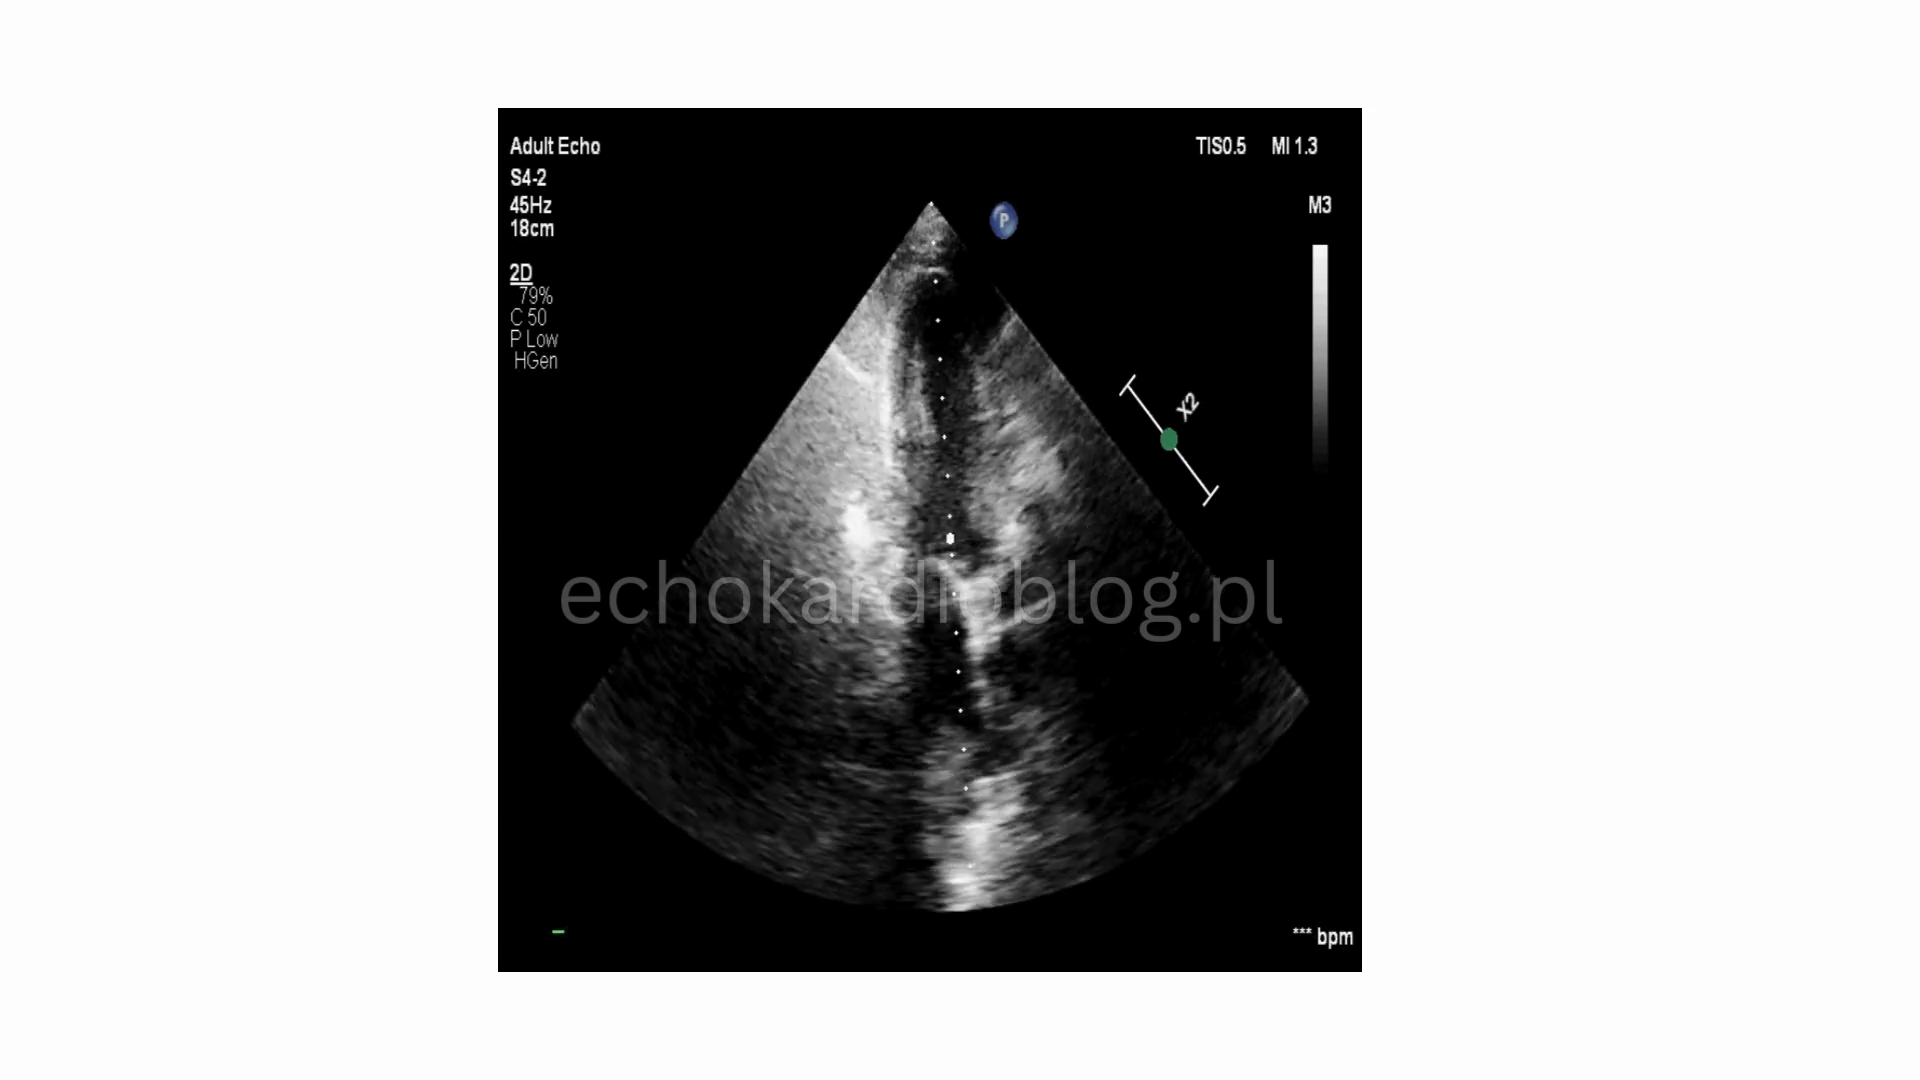

Kardiomiopatia złamanego serca (Tako-tsubo) może wystąpić bez uchwytnego stresora i bez bólu w klatce piersiowej. Może jej towarzyszyć wysokie stężenie D-dimerów, co odzwierciedla burzę katecholaminową i rozlane uszkodzenia śródbłonka. W takich sytuacjach echokardiografia ma istotne znaczenie zarówno dla rozpoznania jak i oceny procesu zdrowienia.

Tako-tsubo cardiomyopathy may occur without an identifable stressor and wihout chest pain. It may also be assiociated with elevated D -dimer levels, reflecting a catecholamin storm and widespread endothelial infury. In such situations, echocardiography remains crucial both for diagnosis and for assessing recovery.